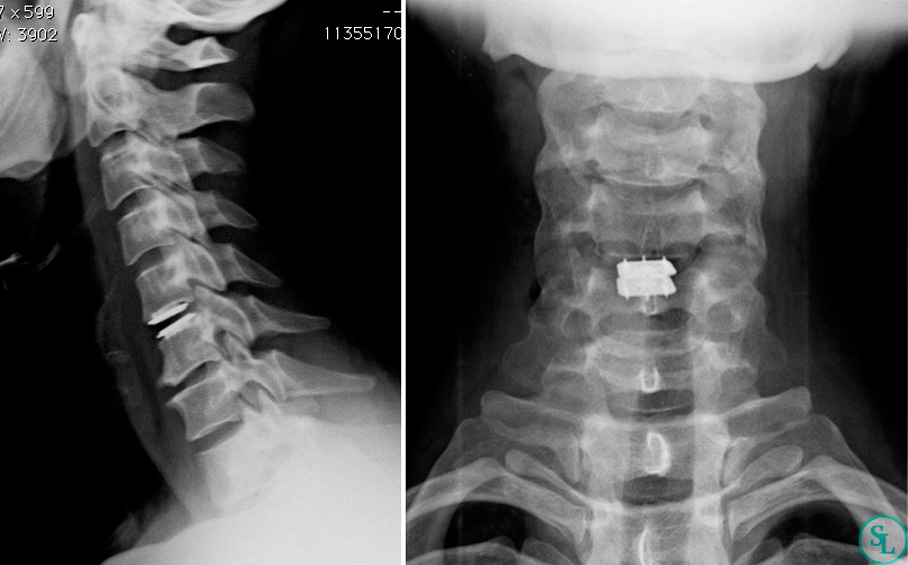

Протяженный стеноз шейного отдела позвоночника на уровне С3–С6. Цервикальная миелопатия на фоне стеноза спинального канала высокой степени тяжести. Диагностированный ранее стеноз спинального канала на уровне L3/L4 и L4/L5.